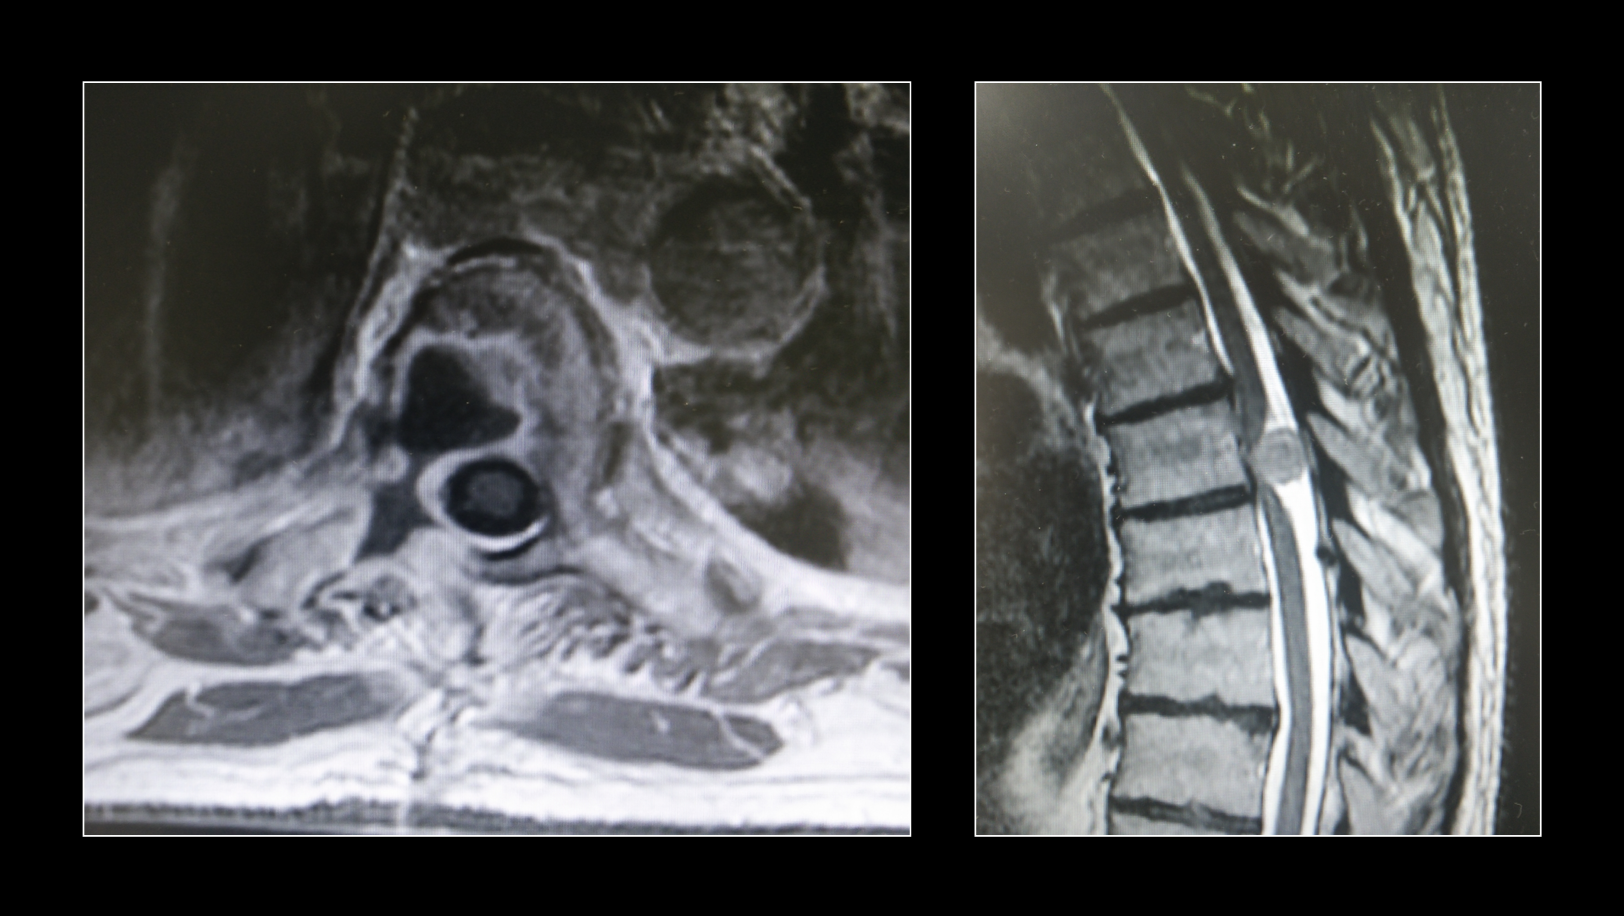

Tumores del raquis vertebral

Las vértebras, nervios u estrictiras de la columna vertebral, como el resto de las estructuras del cuerpo humano, pueden desarrollar tumores. Estos tumores, dependiendo de localización y tamaño, puede ser extirpados mediante cirugía.